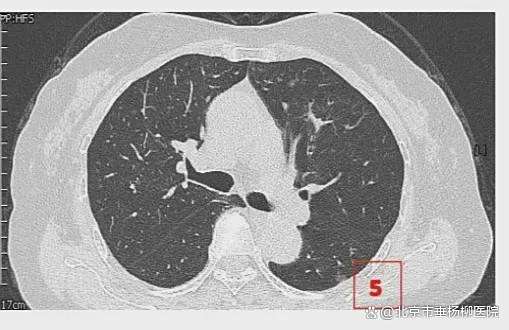

患者女性,71岁,因“发现左肺多发结节2周”入院。胸部CT提示左肺多发磨玻璃结节,较大者位于左肺上叶,呈类圆形,边界清晰,最大直径约9mm。该CT表现高度提示恶性可能。鉴于患者结节数量较多,为减少术中肺组织损伤,术前于CT引导下行经皮肺结节定位术,继而实施胸腔镜下左肺楔形切除术。术中共切除肺部结节6枚。术后病理示:左肺上叶较大结节(4号)为微浸润腺癌,其余5枚结节均为原位癌。患者术后恢复良好,于术后第1天拔除胸腔引流管,第4天顺利出院。

影像资料